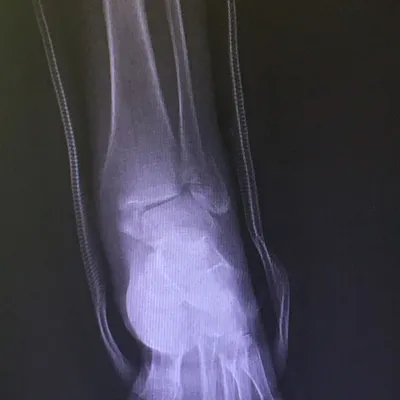

Both the lateral and medial malleolus with fractures with the lateral malleolar fracture classified as a Weber B (at the level of the ankle joint) and the medial malleolar fracture almost transverse (Left x-ray). This is indicative of a Supination External Rotation (SER IV) injury. The fractures are repaired using open reduction with internal fixation (ORIF) technique and fixated with screws and a surgical fractue plate located at the fibular (Right x-ray).

A bimalleolar fracture is a fracture of the ankle that involves the lateral malleolus and the medial malleolus. Studies have shown that bimalleolar fractures are more common in women, people over 60 years of age, and patients with existing comorbidities. Surgical treatment will often be required, usually an Open Reduction Internal Fixation (ORIF). This involves the surgical reduction or realignment of the fracture followed by the implementation of hardware to aid in the healing of the fracture. Usually a plate and screws will be used on the fibular fracture and screws, screws and pins, pins or tension band will most commonly be used on the medial malleolus fracture. A bimalleolar "equivalent" fracture is a fracture of the fibula with rupture of the superficial and deep portion of the deltoid ligaments leaving the medial malleolus intact. Surgical management is common due to the instability of the fracture and displacement of the talus laterally.

The x-ray images below demonstrate another case of a bimalleolar ankle fracture in both and oblique view (left) and anterior - posterior view (right).